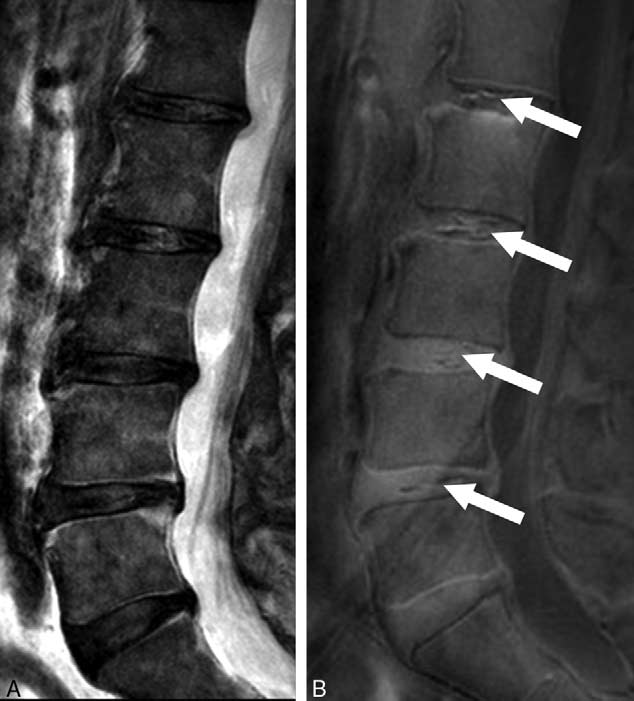

MRI of the lumbar spine of a subject with no chronic low back pain.

(Left) T2-weighted MRI noting multilevel disc degeneration and Modic changes.

(Right) Ultra-short time-to-echo (UTE) MRI noting no UTE disc sign (UDS).